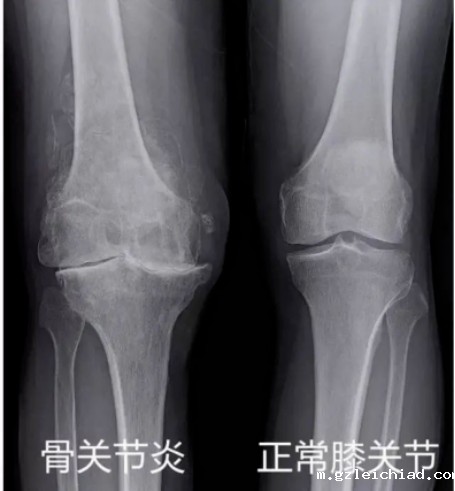

4.去医院拍个膝关节X光片发现有:关节间隙变窄、软骨下骨硬化和(或)囊性变、关节边缘有骨赘(骨刺)形成。